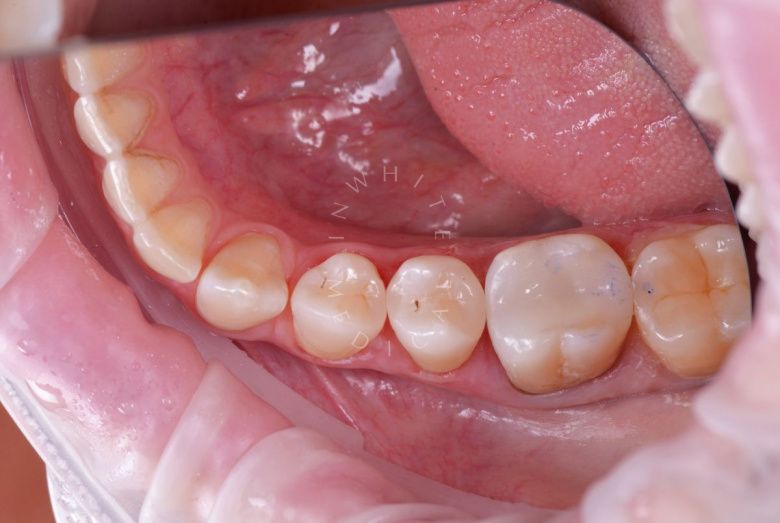

Лечение фиссурного кариеса под увеличением

Восстановление зуба пломбой (лечение фиссурного кариеса) / А16.07.002.015

19 360 ₽